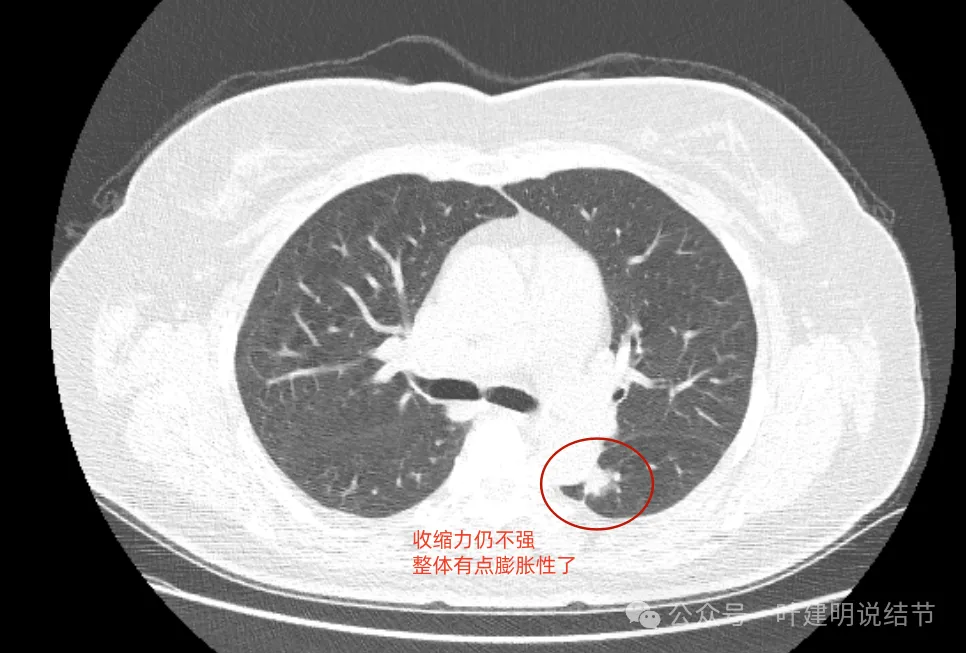

最后看2024年复查的影像:

膨胀性较前明显,基本实性。

与主动脉壁贴得紧了,但褐色所指处边缘还是较为平直。

与主动脉壁之间紧贴了,对侧出现了细毛刺,整体基本都是实性密度了。

表面不平,密度高,与主动脉间隙消失。

现在较2年前有进展,显示了更多的恶性影像特征,整体密度也增加,膨胀性也明显起来,并对邻近结构有压迫,表面不平毛糙。持续存在的实性为主的结节随访进展,并显示出更多恶性特征,那就得高度怀疑恶性,而且不宜再随访了。